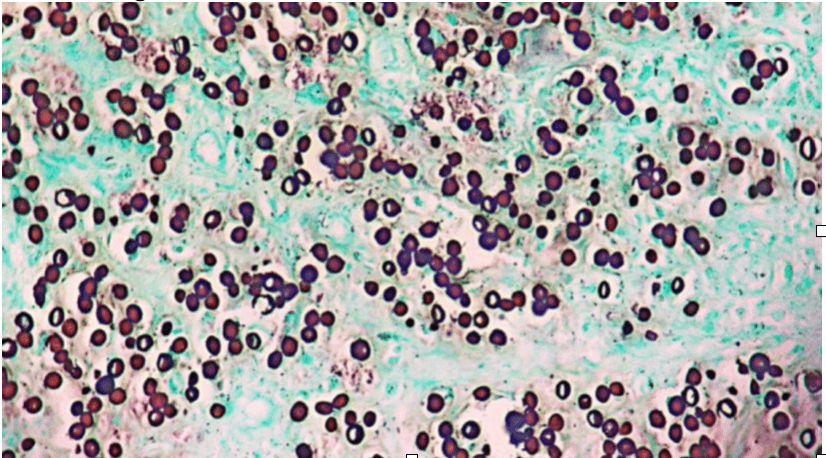

A skin biopsy is performed. Grocott methenamine silver (GMS) staining reveals oval yeast-like structures with birefringent membranes, arranged both isolated and in chains resembling “Rosario beads.”

The causative organism is Lacazia loboi (a name proposed to replace older designations). The organism has not been isolated in culture, but sequencing data place it close to Paracoccidioides. Histopathology is the key diagnostic feature: thick-walled yeast-like cells that appear isolated or in chains connected by narrow bridges, producing the characteristic “Rosario beads” appearance on silver stains such as GMS.

The “Rosario beads” pattern on GMS (chains of thick-walled yeast-like cells) is a key histopathologic clue.